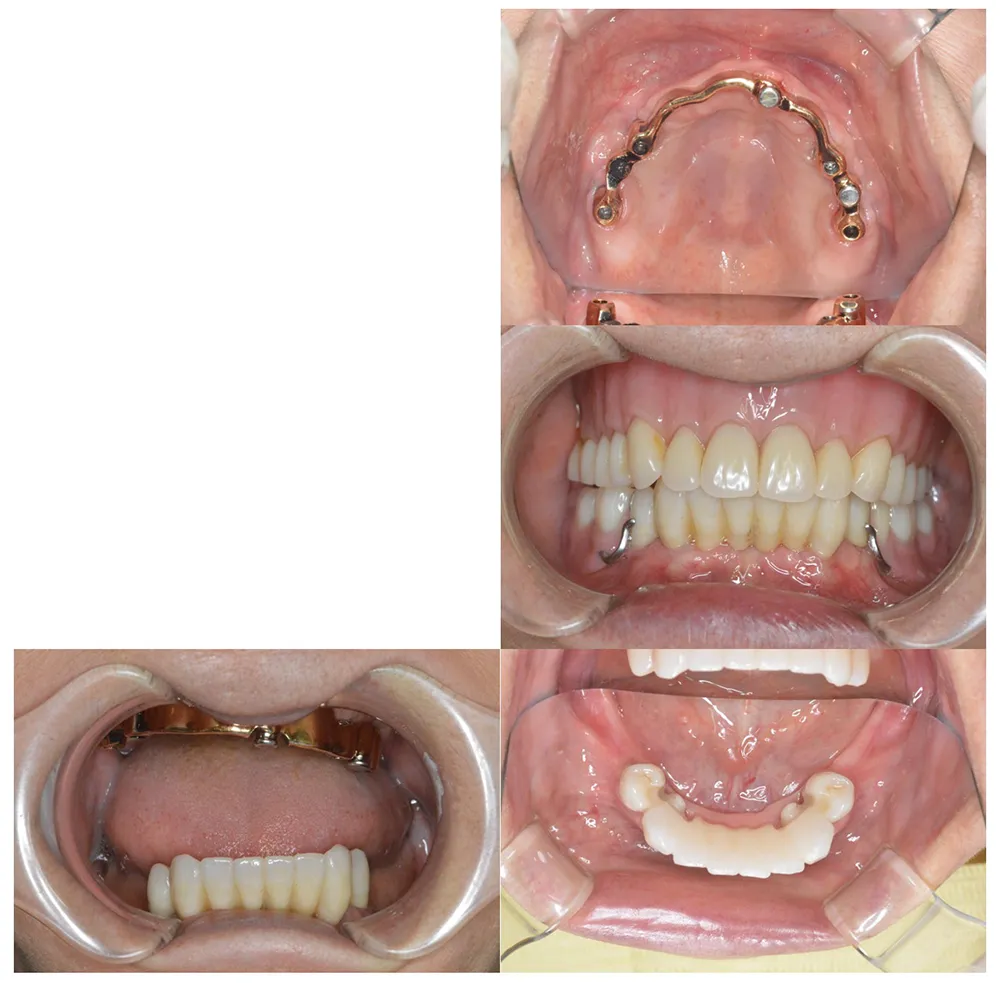

重度の歯槽膿漏のケース

■治療前

■治療後

治療のポイント

上下に入れ歯を入れていましたが、ここ数年しっかりと噛む事がなかった患者様です。何でもおいしく食事ができるようになりたいと希望され、来院されました。

治療法としては、最小限のインプラントの本数で対応ができるように、オールオンフォーを意識した治療法で対応させて頂きました。

| 主訴 | 噛めない |

| 治療方法 | 上顎8本、下顎6本のインプラントを埋入し固定性の入れ歯で治療した |

| 治療期間 | 約1年 |

| 通院回数等 | 20回 |

| 費用 | 上顎4,130,000円 下顎3,630,000円(税込) |

| リスク・副作用 | 治療後に一時的に腫れることがある |